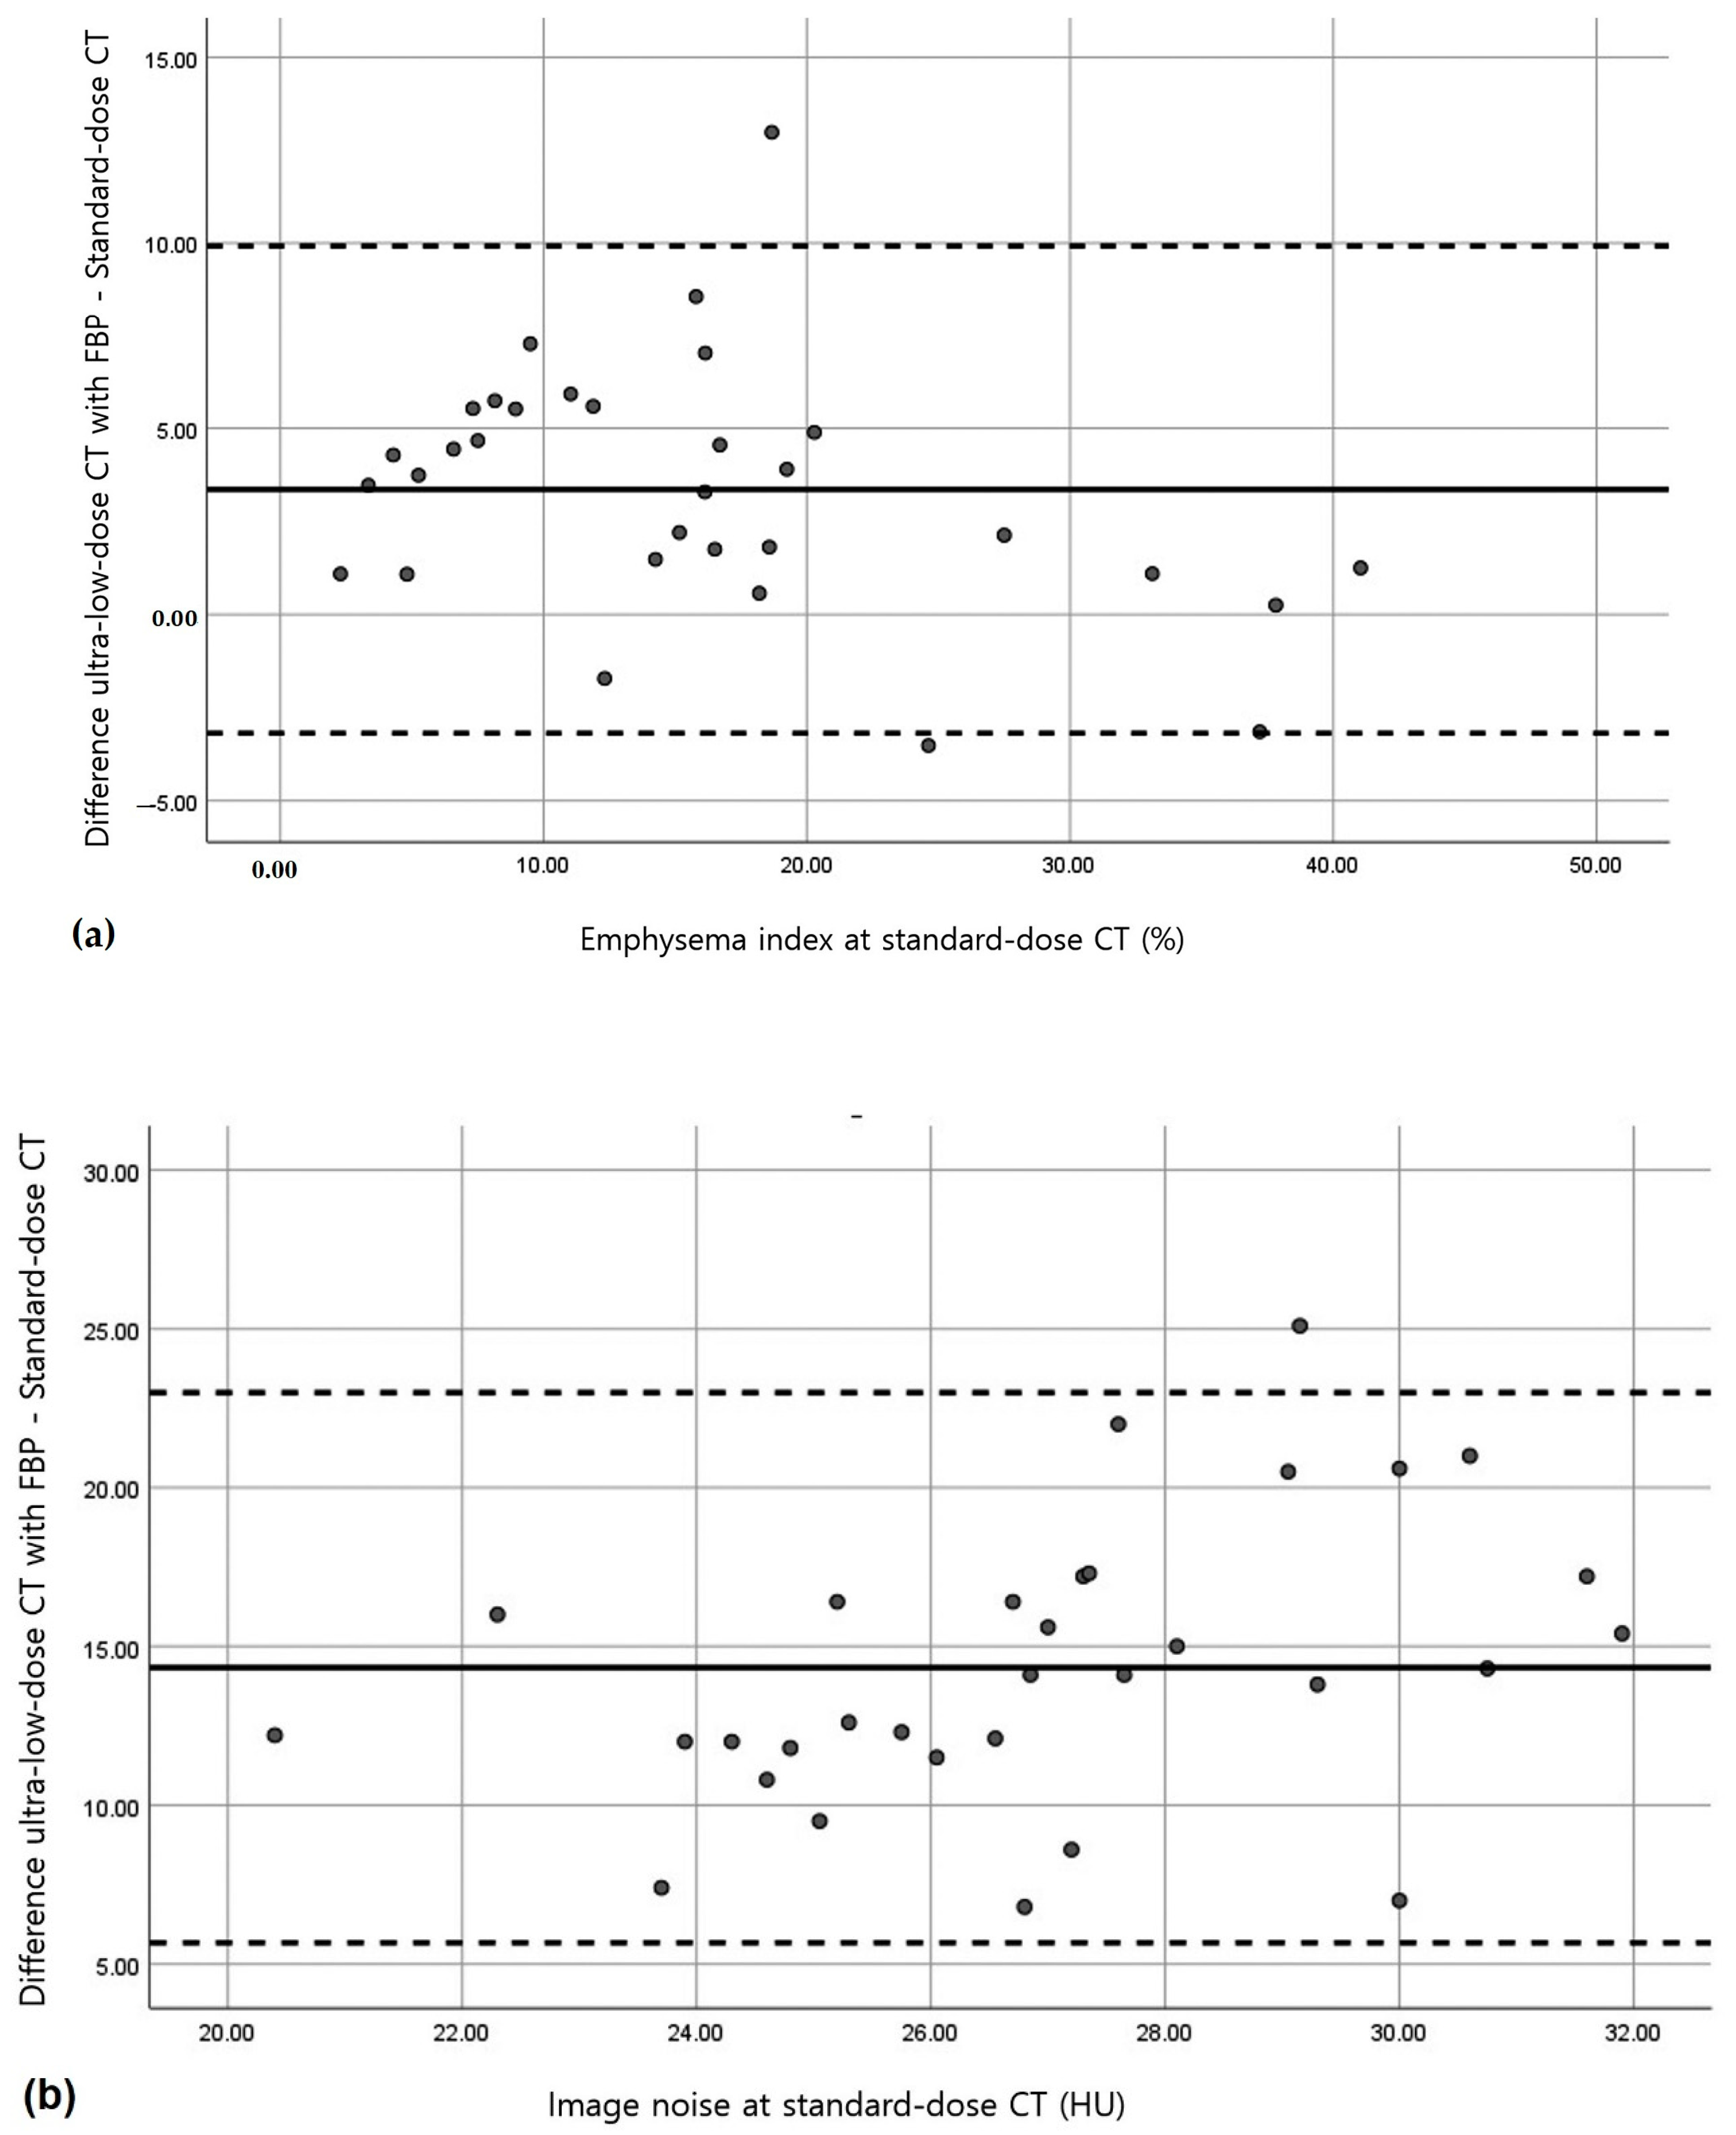

3.2. Quantitative Measurements of Standard-Dose and Ultra-Low-Dose CT

4. Discussion